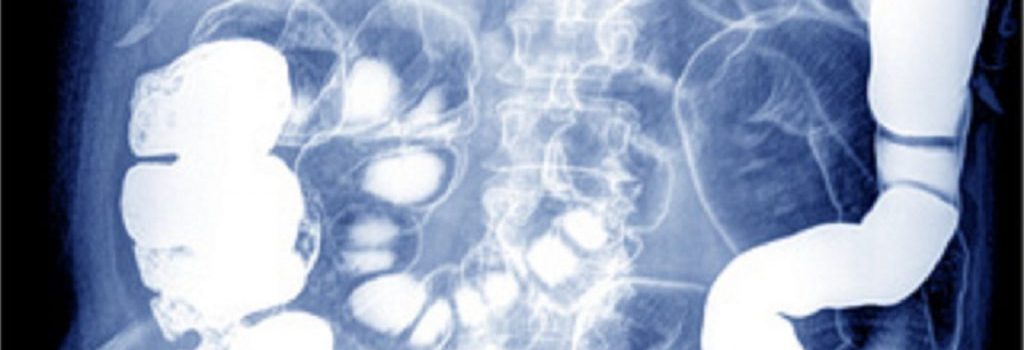

Der Stuhlgang ist ein direktes Spiegelbild der Darmgesundheit – und damit ein zentrales Signal für den Zustand des gesamten Verdauungssystems. Farbe, Form, Geruch, Konsistenz und Häufigkeit liefern Hinweise darauf, ob die Verdauung reibungslos funktioniert oder ob eine Störung im Gastrointestinaltrakt vorliegt. Trotzdem fehlt vielen Menschen ein klares Verständnis davon, was tatsächlich als normaler Stuhlgang gilt. … Stuhlgang: Was ist normal? Farbe, Form, Durchmesser, Häufigkeit weiterlesen